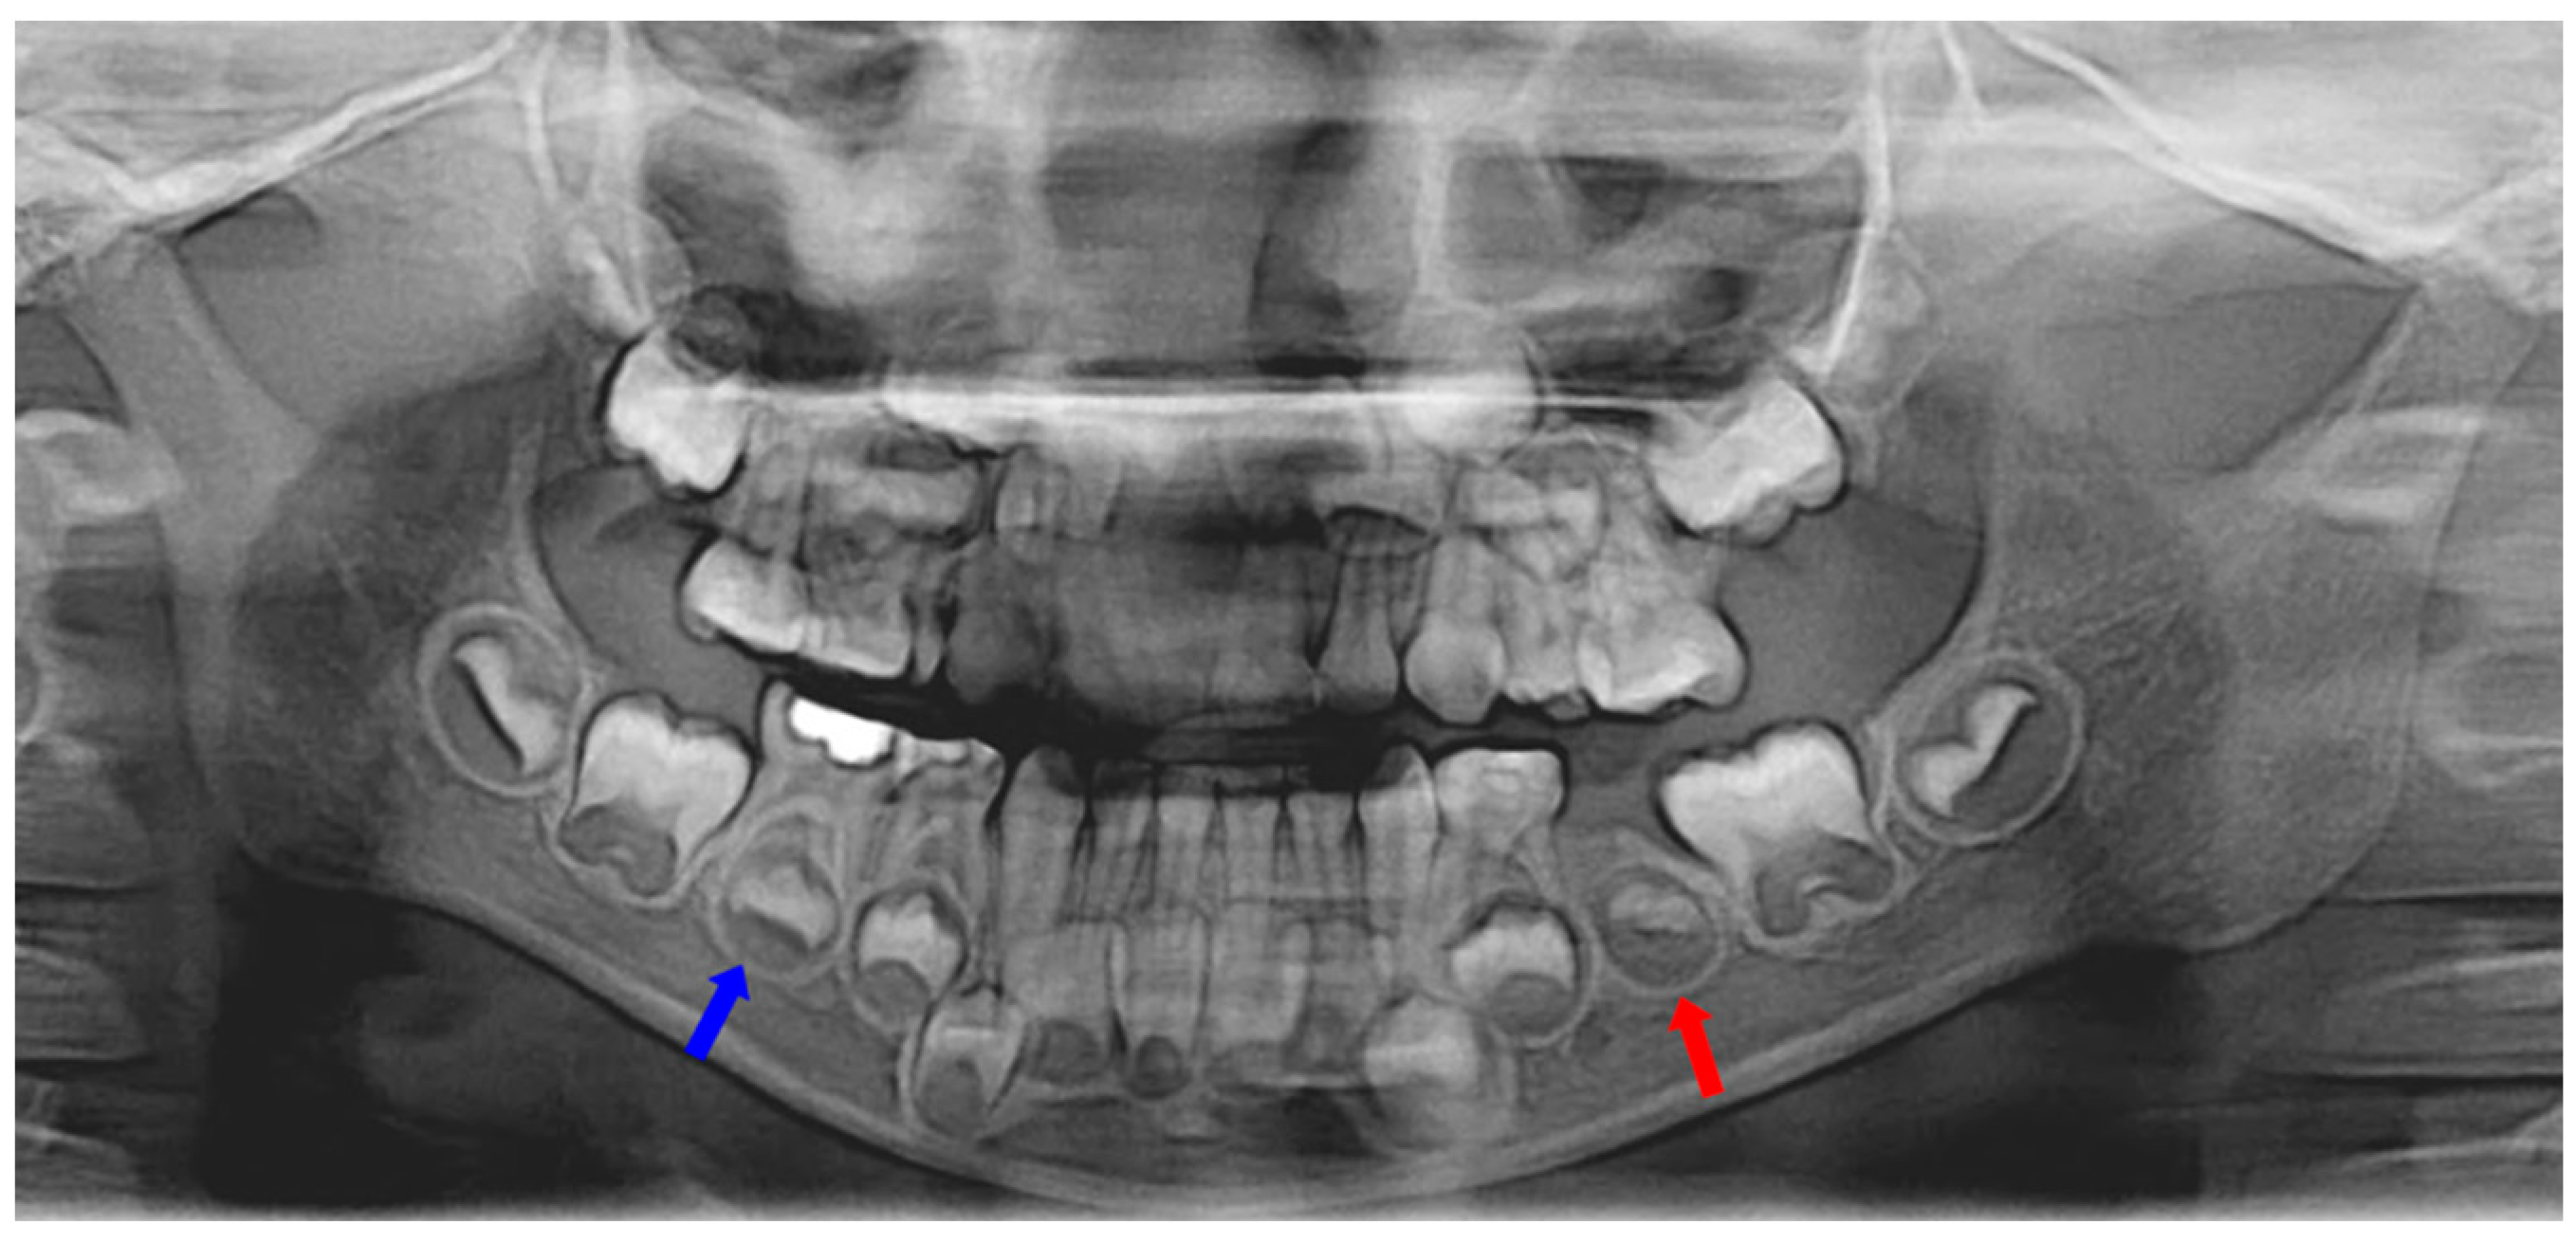

Two months after extraction, most of the extruded material was resorbed, but there was a small amount left near the successive tooth germ (Figure 1b). Eleven months after extraction, radiological examination showed the underdevelopment of permanent successive tooth germ compared to the opposite side (Figure 1c and Figure 2).

Figure 2.

Eleven months after tooth extraction. Panoramic radiograph. The underdevelopment of the left mandibular second premolar tooth germ (red arrow) was observed compared with the opposite one (blue arrow).

A band and loop space maintainer was delivered after the eruption of the left mandibular first molar. Three years after the extraction, the development of the successive permanent tooth was observed (Figure 1d). Four years post-extraction, the successive tooth was in the pre-eruptive phase, with continuous growth and pre-eruptive movement in the alveolar bone, similar to those in the opposite tooth (Figure 3).

Figure 3.

Four years after tooth extraction. Panoramic radiograph. Development of successive permanent tooth was observed (pre-eruptive phase).